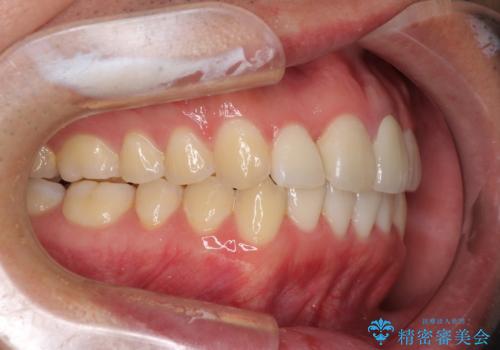

前歯の歯並びとクラウンを改善 インビザラインとオールセラミック

- 前歯の歯並びと不自然な色をした前歯のクラウンを気にして来院された患者様です。

上下前歯の歯列不正はインビザラインにより歯列を整え、その後に、前歯をオーダーメイドタイプのオールセラミッククラウンにて補綴治療することとしました。

初診時には、歯並びを整えることのみを検討されていましたが、歯列が整うにつれて不自然な色合いが気になるようになり、矯正治療を行ってから補綴治療をする計画を受け入れてくださいました。

口元の印象が明るく変わり、患者様には大変満足していただきました。